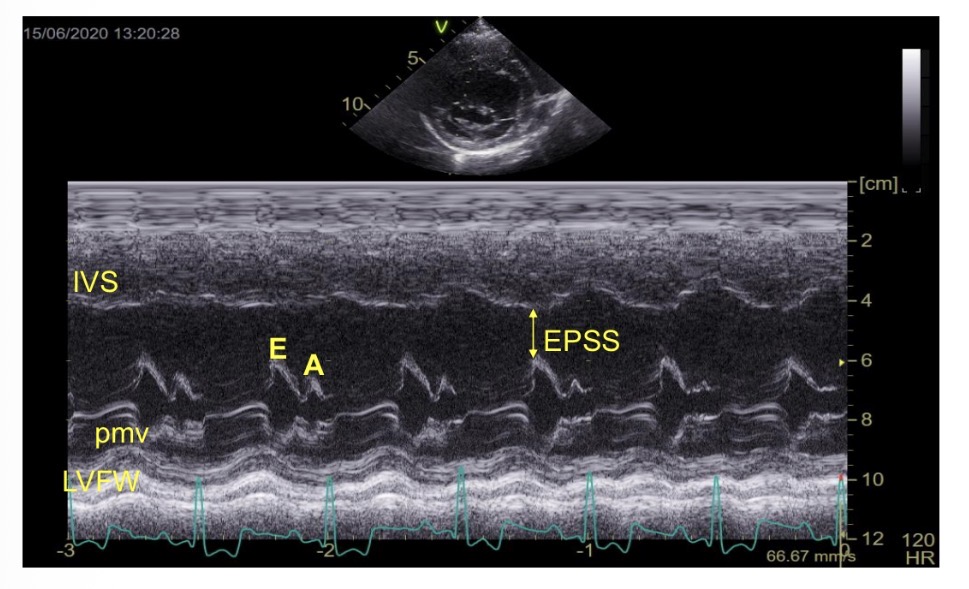

What does M-mode echocardiography show

Wall thickness/position over time/ ECG

How many times does M valve open in systole

2

What is EPSS

E point to septal separation

E peak meaning

Early filling - mitral valve opening

A peak meaning

A contraction